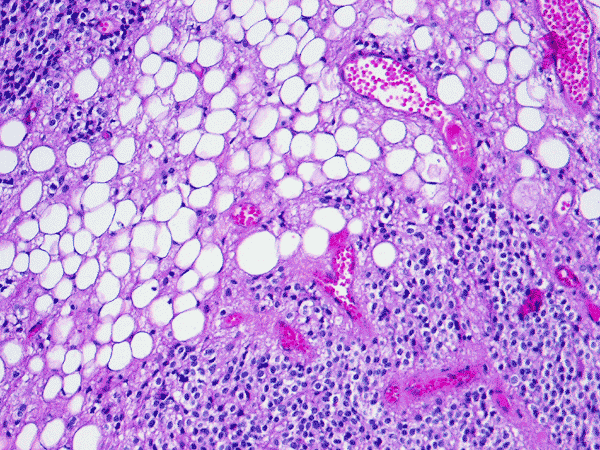

Pathology of the case:  The specimen was fragments of soft tan tissue. The lesion is a cellular neoplasm with solid sheets of cellular component admixed with irregular islands of lipidized cells with morphology of mature adipocytes (Panel A). The two components are well demarcated from each other (Panel B). The cellular component contains predominantly of polygonal cells with round nuclei and minimal nuclear pleomorphism (Panel C and D). Although a perinuclear halo is present in most of the tumor cells, the cytoplasm is not optically clear in some tumor cells and contains a amphophilic, finely granular cytopalsm. Scant amount of neuropils are present. On immunohistochemistry, the cellular component is strongly immunoreactive for syanptophysin ((Panel E).  Immunoreactivity for NeuN is weak and heterogeneous. Some entrapped reactive astrocytes are demonstrated by immunohistochemistry for glial fibrillary acidic protein but both cellular and adipose cell-like components are negative. No immunoreactivity for neurofilament proteins is demonstrated in the tumor cells.

Cerebellar liponeurocytoma have been described in the cerebellar vermis, hemispheres and as tumor that grow into the cerebellar pontine angle. Histologically, the neuronal/neurocytic component is composed of sheets of uniform polygonal cells with round nuclei. Distinct perinuclear halo similar to those being seen in oligodendroglioma and central neurocytomas are present in the neuronal/neurocytic component. This would lead to a honey comb pattern under low- or medium-magnification.  Some of these cells may also have amphophilic granular cytoplasm. Neuropil formation can be focally seen. The lipidized component is morphologically indistinguishable from mature, adult type of adipose tissue  in other part of the body. Histologic variation between different tumors do not appear to be substantial.

Immunohistochemistry, the neuronal/neurocytic component is strongly reactive for synaptophysin and S100. Some of them may also express glial fibrillary acidic protein (GFAP). The lipidized cells, however, has been characterized as having both neuronal and glial phenotype and are suggestive of lipidized cells of neuroepithelial origin 3, 5.